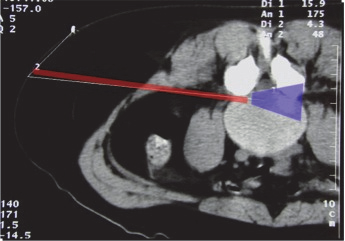

It is the “Kambin triangle” (the safe corridor to the lumbar disc between the exiting nerve root and the superior facet) which reminds us of his pioneering work (Figure 9).

Figure 9: Kambin’s triangle for a safe posterolateral approach.